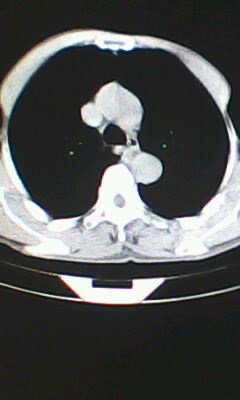

标题: CT26182:男 胸憋 无其它异常症状

胸廓呈桶状,双膈低平,肺实质及纵隔未见明显异常密度灶考虑肺气肿.

肺气肿

以下是引用ctkz987在2010-5-5 21:30:00的发言:[br]胸廓呈桶状,双膈低平,肺实质及纵隔未见明显异常密度灶考虑肺气肿.

弥漫性肺气肿 但内胆管轻度扩张

临床诊断:copd

慢阻肺是临床诊断,未见明显异常。